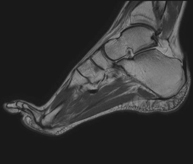

- RM Tobillo

Exploración para el estudio de la articulación y sus frecuentes lesiones de ligamentos (esguinces) así como de la afectación de otras estructuras como el cartílago o el hueso. También es de gran utilidad para diagnosticar alteraciones en el tendón de Aquiles (tendinitis, roturas). Duración de aproximadamente 20 minutos. No emplea radiación ionizante.

- RM Pie

Exploración para el estudio de lesiones en tendones músculos y pequeñas articulaciones. Permite valorar con eficacia las lesiones en el cartílago. También es de mucha utilidad para completar la exploración ecográfica previa. No emplea radiación ionizante. Tiene una duración aproximada de 20 minutos.